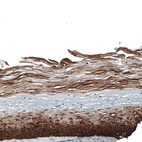

Immunohistochemistry analysis in human prostate and kidney tissues using AMAb91549 antibody. Corresponding KRT5 RNA-seq data are presented for the same tissues.